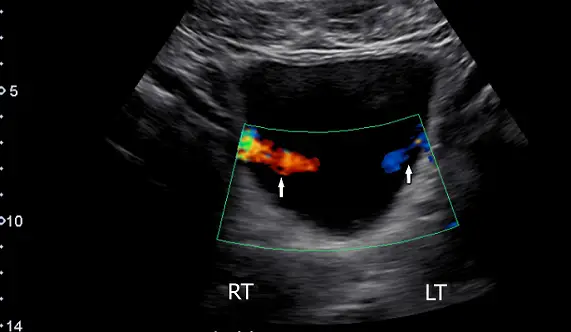

下圖為膀胱的彩色都卜勒影像(橫向掃描),箭號所指的是:

- 影像模式:骨盆腔橫切面(Transverse scan)之彩色都卜勒超音波影像。

- 解剖構造與發現:圖中中央大片無回音(anechoic,黑色)區域為充滿尿液的膀胱。在膀胱後側壁偏外側處(相當於膀胱三角 trigone 的兩側輸尿管開口位置),可見兩道分別呈現紅色與藍色的彩色血流訊號(如白色箭頭所指),向膀胱腔內噴射。

- 彩色都卜勒意義:此處的彩色訊號並非實質血管內的血流,而是代表「流體(尿液)的動態移動」。紅色與藍色僅代表尿液噴射方向相對於超音波探頭的角度差異(朝向或遠離探頭)。這種陣發性進入膀胱的彩色訊號,即為典型的輸尿管噴尿現象。

- (A) 輸尿管尿液射入膀胱(ureteric jet):正確。當輸尿管透過蠕動將尿液排入膀胱時,由於噴射出的尿液與膀胱內原有的尿液在流速與比重上產生差異,在彩色都卜勒模式下會呈現明顯的噴射狀訊號。圖中箭號所指正是兩側出現的 ureteric jet。